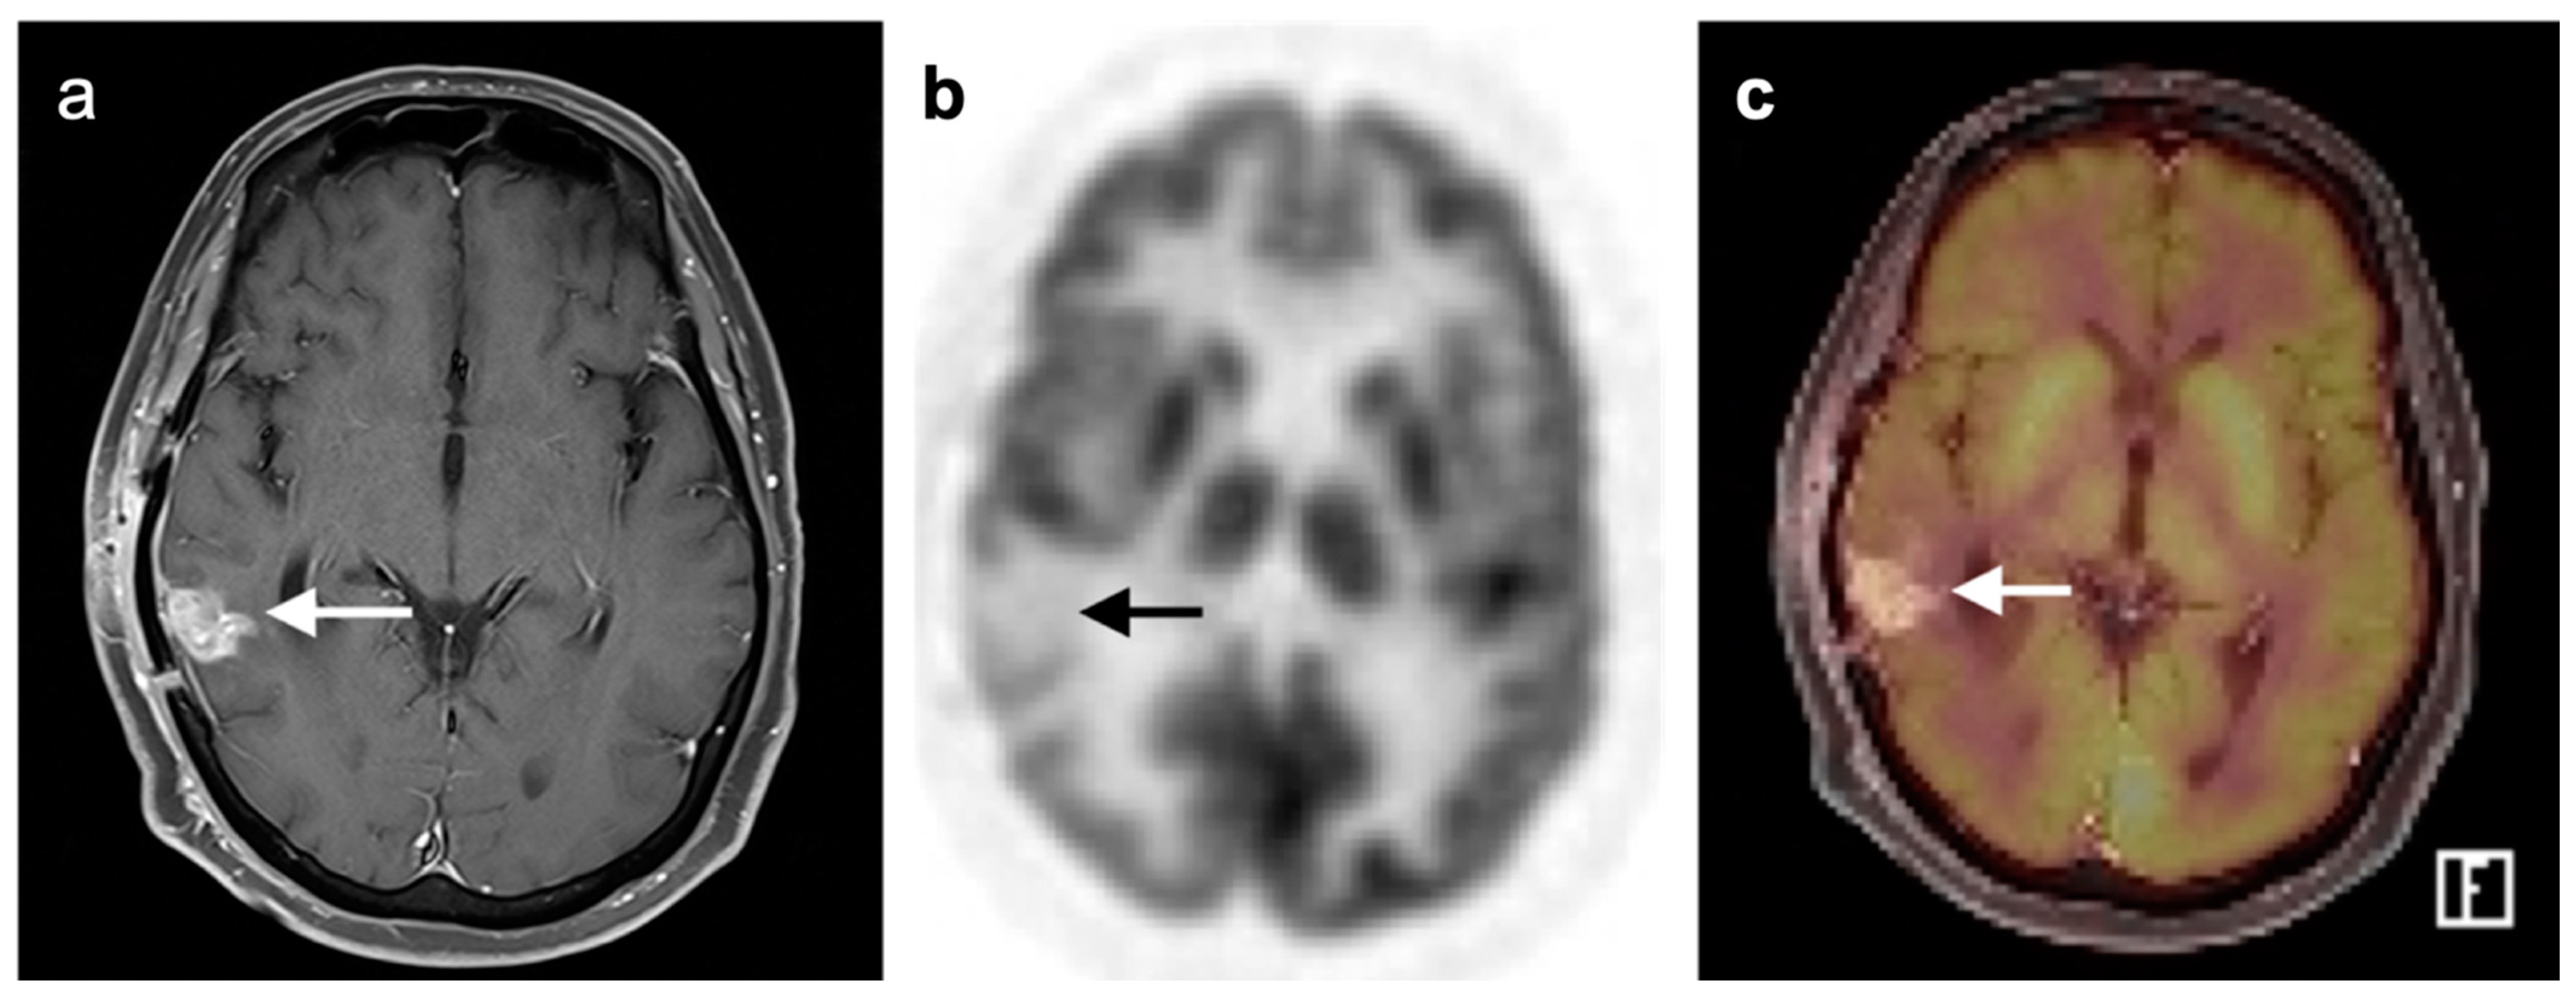

- Marcus, C.; Feizi, P.; Hogg, J.; Summerfield, H.; Castellani, R.; Sriwastava, S.; Marano, G.D. Imaging in Differentiating Cerebral Toxoplasmosis and Primary CNS Lymphoma With Special Focus on FDG PET/CT. AJR Am. J. Roentgenol. 2021, 216, 157–164. [Google Scholar] [CrossRef]

- Galldiks, N.; Langen, K.-J.; Albert, N.L.; Chamberlain, M.; Soffietti, R.; Kim, M.M.; Law, I.; Le Rhun, E.; Chang, S.; Schwarting, J.; et al. PET imaging in patients with brain metastasis-report of the RANO/PET group. Neuro-Oncology 2019, 21, 585–595. [Google Scholar] [CrossRef]

- Chao, S.T.; Suh, J.H.; Raja, S.; Lee, S.-Y.; Barnett, G. The sensitivity and specificity of FDG PET in distinguishing recurrent brain tumor from radionecrosis in patients treated with stereotactic radiosurgery. Int. J. Cancer 2001, 96, 191–197. [Google Scholar] [CrossRef]

- Horky, L.L.; Hsiao, E.M.; Weiss, S.E.; Drappatz, J.; Gerbaudo, V.H. Dual phase FDG-PET imaging of brain metastases provides superior assessment of recurrence versus post-treatment necrosis. J. Neurooncol. 2011, 103, 137–146. [Google Scholar] [CrossRef]